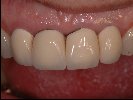

- Vollkeramische Restauration auf vollkeramischen Abutment

- Vollkeramische Restauration auf Implantat